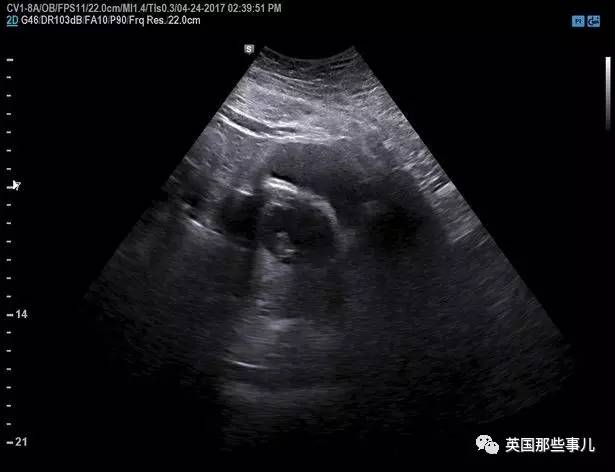

Monica第一次怀孕,在孩子12周的时候去检查,

结果经过扫描发现,她的孩子缺少一个胳膊,和身体的下半身....

这个孩子最终流产了。

Monica和Sid去做产检,

医生们告诉他们,宝宝目前身体状况一切正常、良好,

他还特别爱动,非常活泼.....